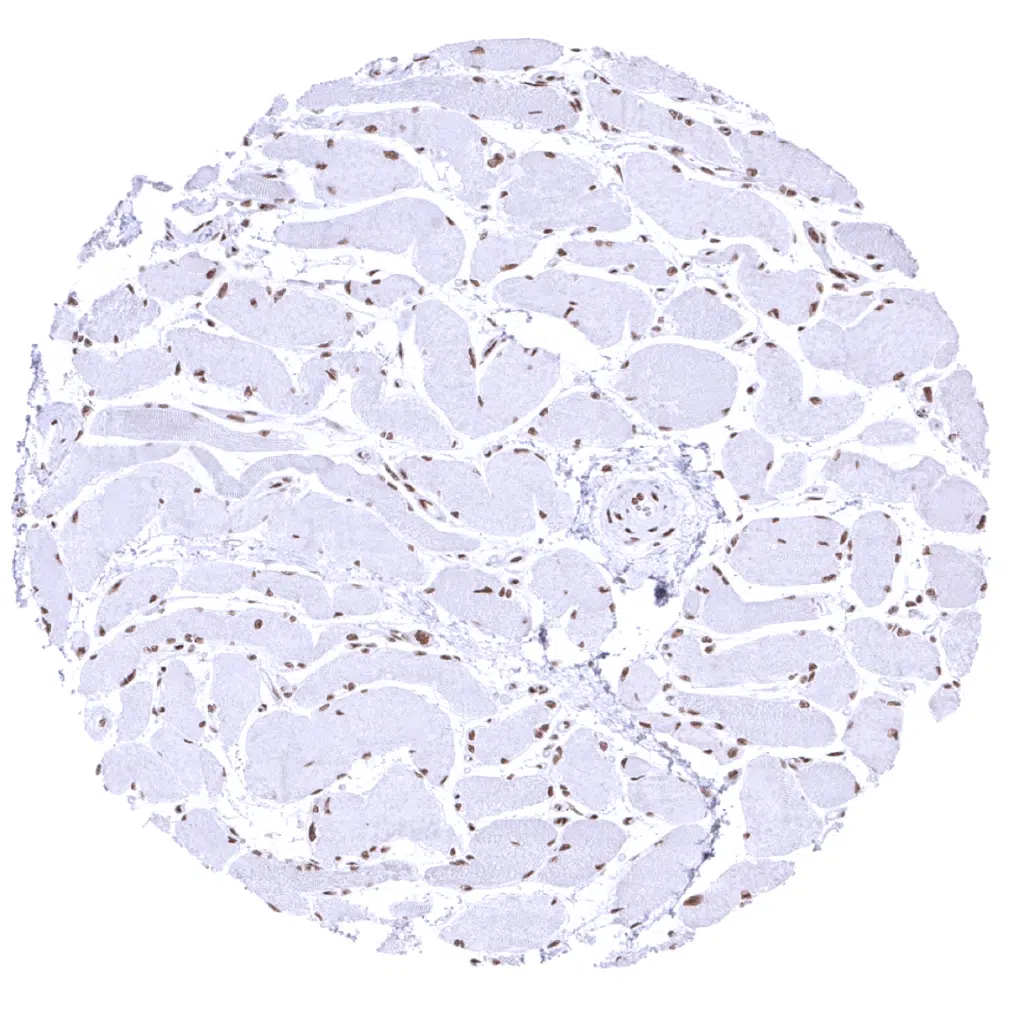

Skeletal muscle